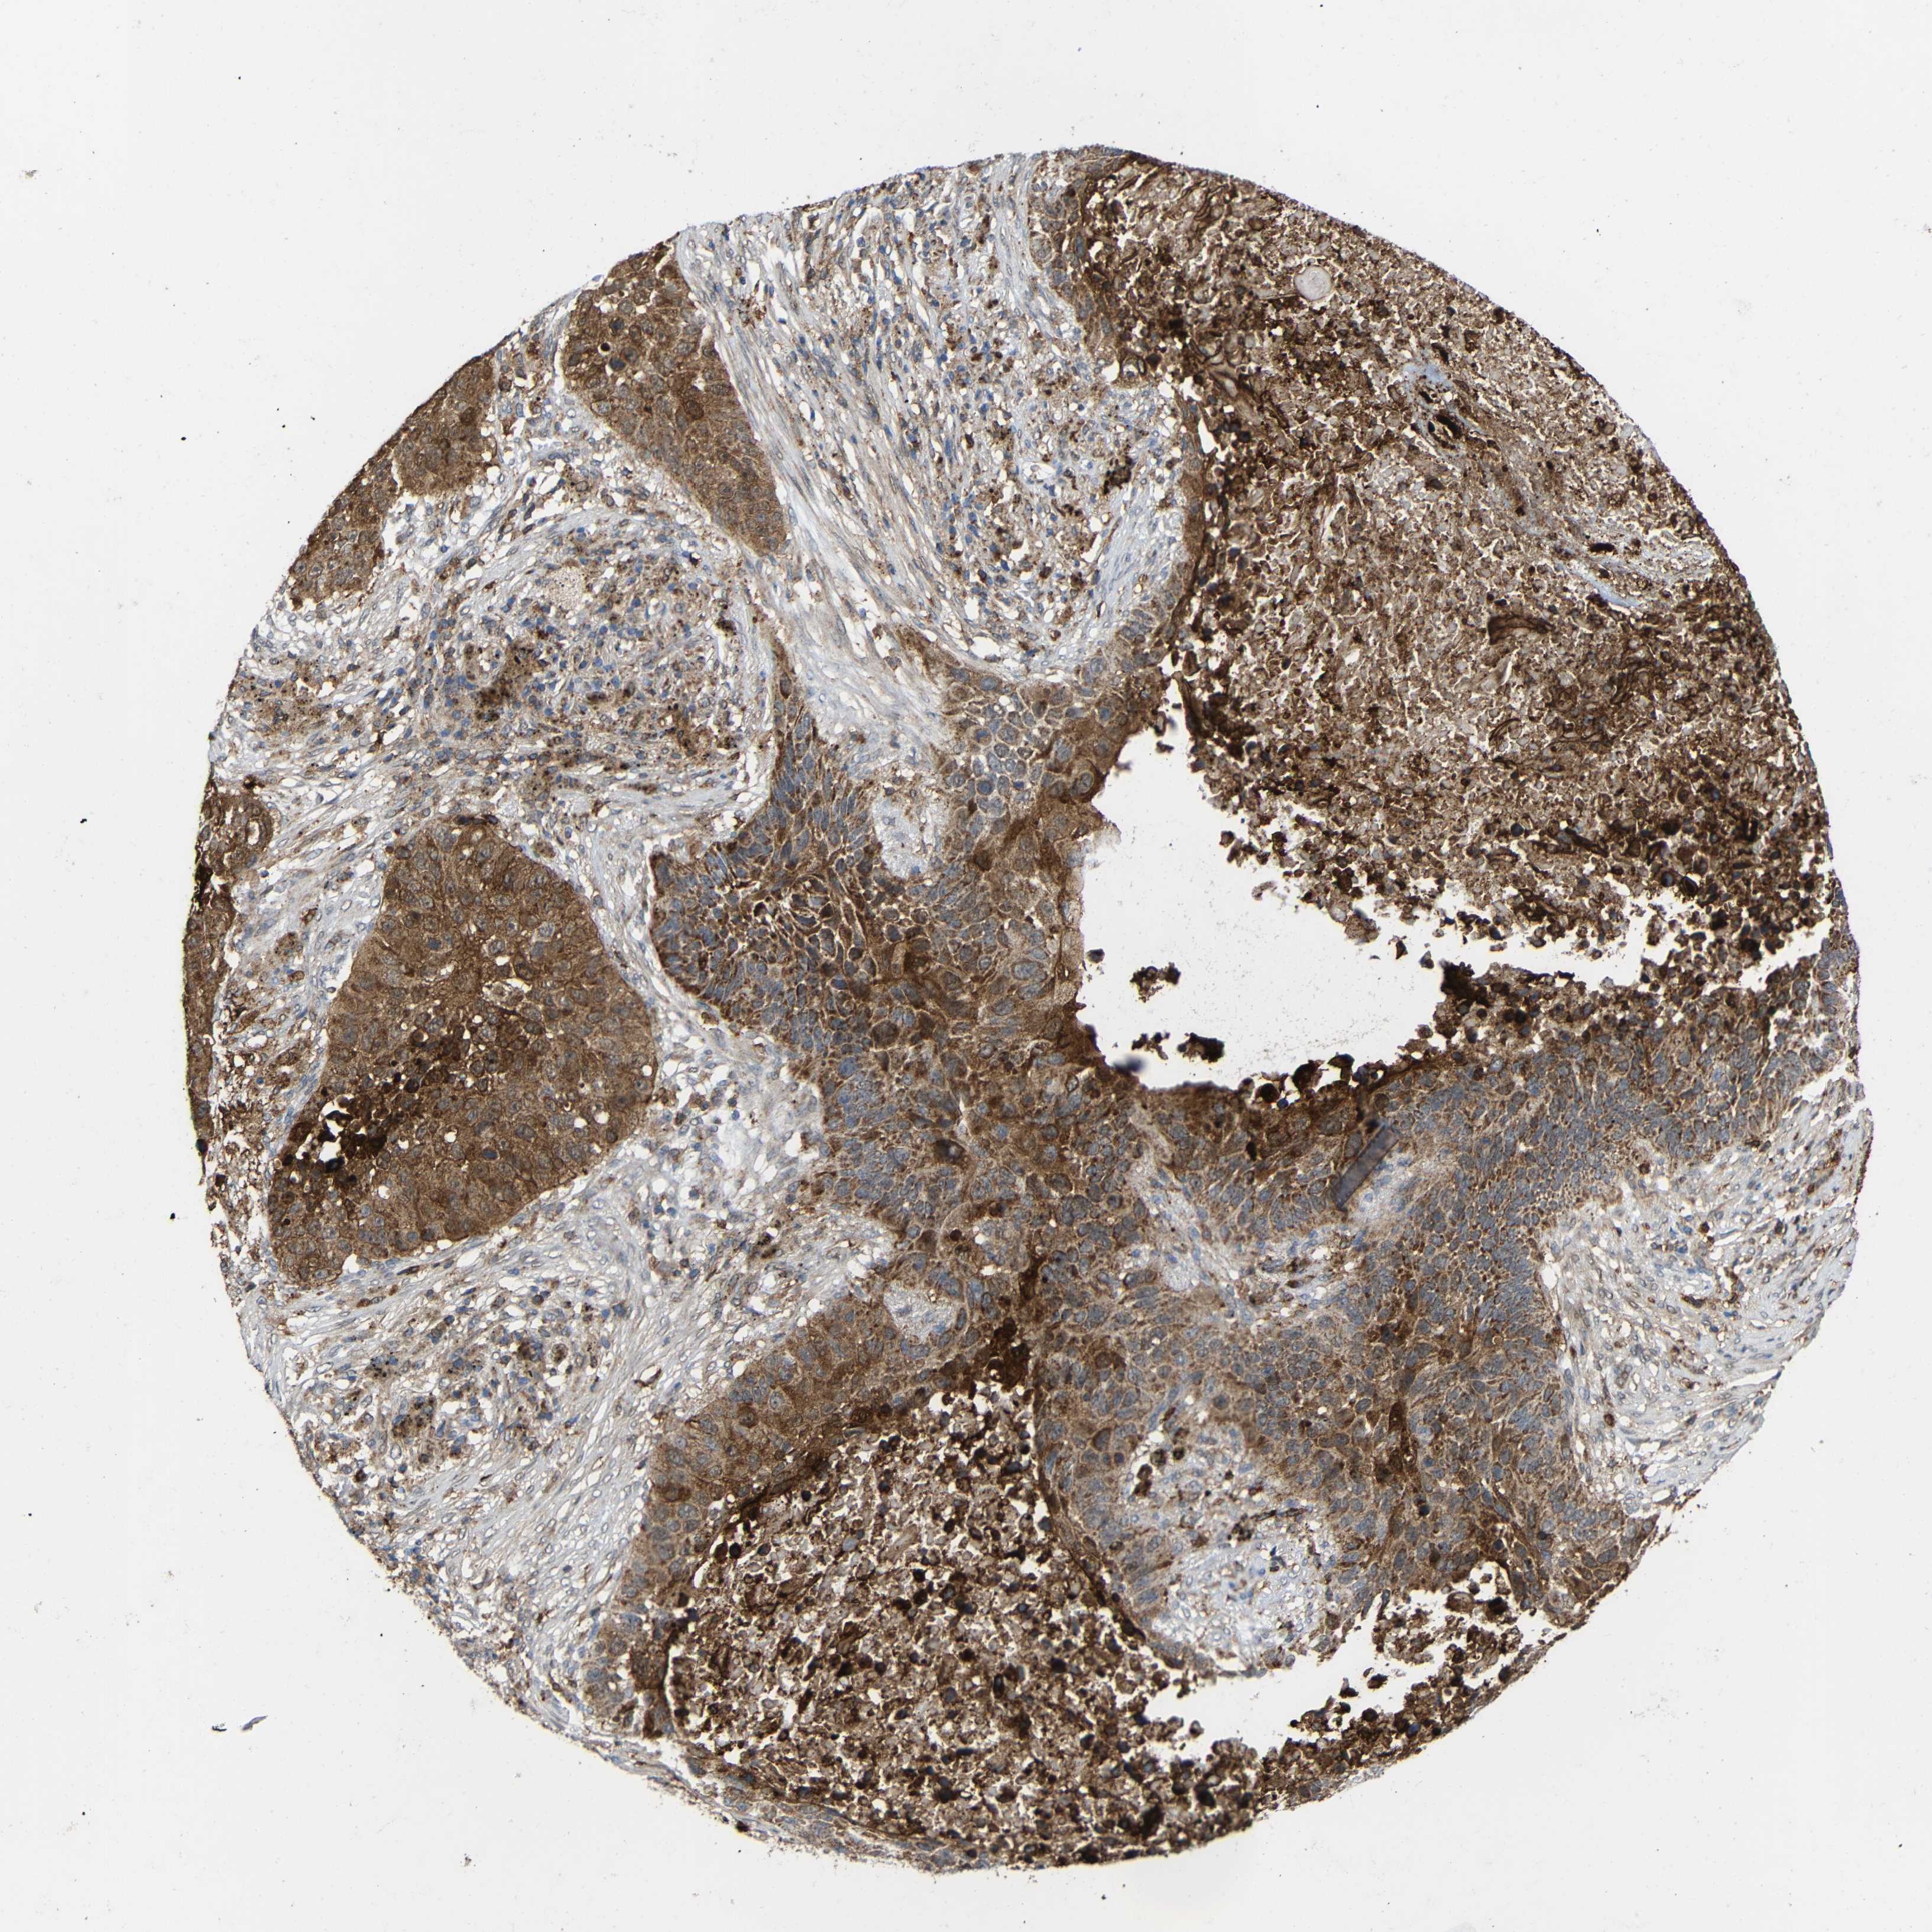

CANCER LUNG CANCER Show tissue menu